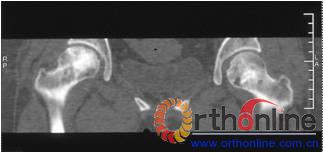

图1 女,22岁,(1)双侧股骨头坏死右侧B型,左侧C1型;(2)打压植骨术(加入BMP2)后5年,CT显示植骨生长良好,关节功能正常(Harris评分96分);(3)术后7年关节功能维持正常,股骨头维持正常外形

图3-1 女,31岁,SARS患者骨坏死,(1)MRI示双侧股骨头坏死,右Ⅱb(B型),左Ⅱc(C1型);(2)打压植骨术(未加BMP2)后坏死修复不完全,仍遗留股骨头软骨下病灶未完全修复, 5年随访关节功能优(Harris评分96分)

图3-2 女,30岁,SARS患者骨坏死,(1)术前MRI示双侧骨坏死;右Ⅱc期C3型,左Ⅱb期B型,打压植骨术(加BMP2),(2)5年后CT显示病灶修复好,关节功能优